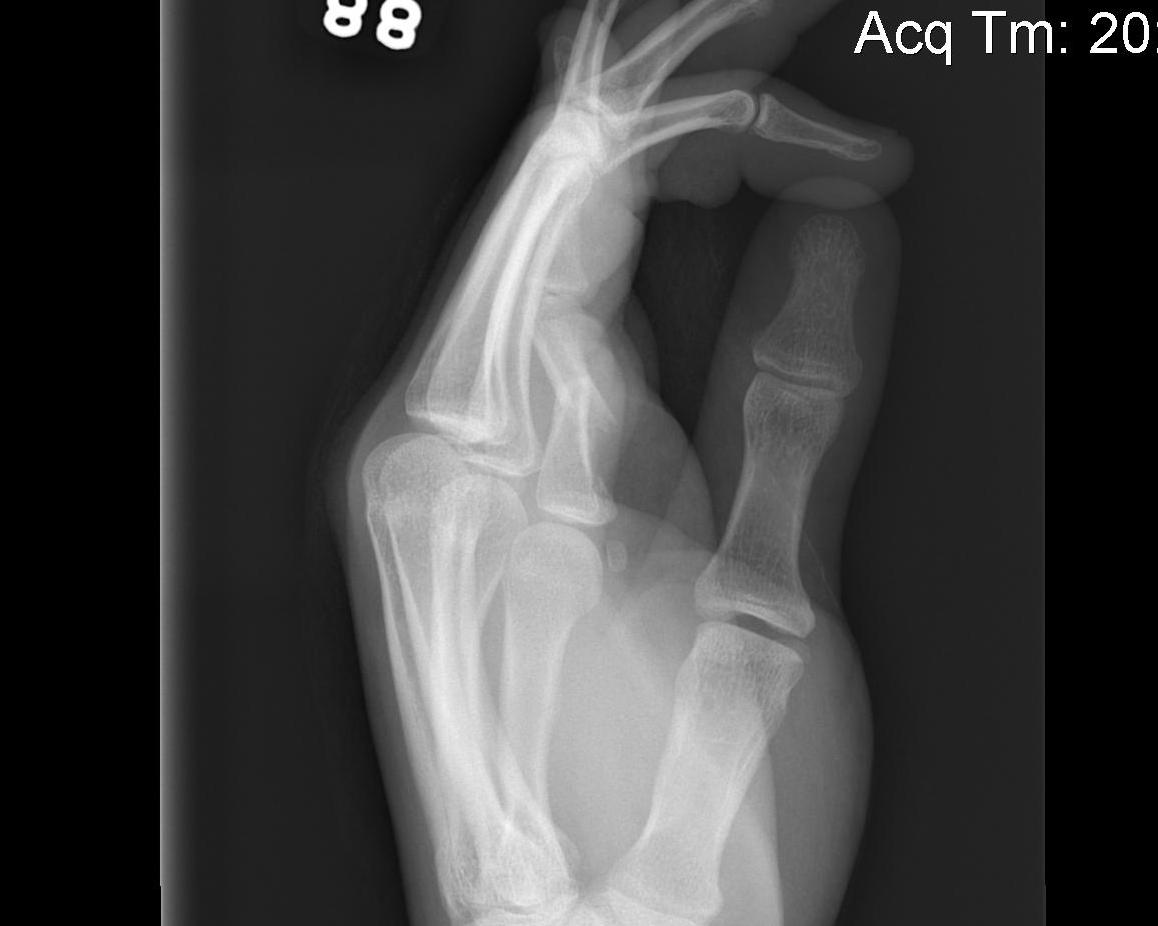

X-rays

3 planes centred on MCPJ middle finger

- AP

- lateral

- oblique

Care to look for subtle evidence joint subluxation